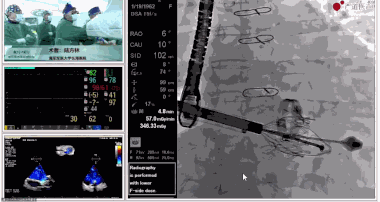

▲瓣膜植入后釋放的過程

▲瓣膜植入后三維超聲影像

▲瓣膜植入后右心室造影

在手術直播中瓣膜植入過程不到10分鐘,手術獲得圓滿成功,充分體現徐志云、陸方林團隊技術精湛,團隊協作默契及器械的優越性。

該例患者返回后當天拔除氣管插管,生命體征穩定,恢復良好。此次會議不僅有最前沿的學術講座,更有3D體驗般的手術直播,為大家第一視角直觀呈現領域新技術、新策略、新思路。